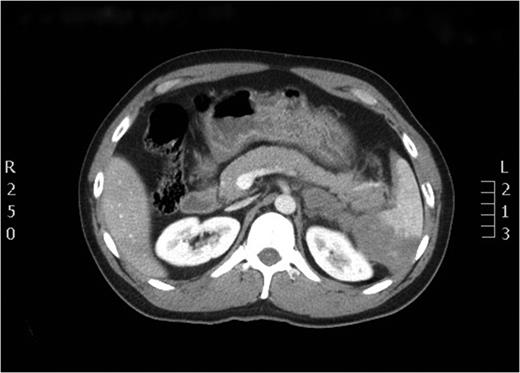

After the secondary survey, the patient was subjected to a computed tomography (CT) study, which showed a Grade IV splenic injury per the American Association for the Surgery of Trauma injury grading score with contrast extravasation (Fig. 1), a lower lobe contusion of the left lung, fractures of the IV and VI–XI ribs on the left side and bilateral iliac wing fractures. The pancreatic parenchyma was well perfused and homogenous in a portal venous phase CT-imaging (Fig. 2).

Axial view of the initial CT scan depicting a normally perfused pancreatic tissue.